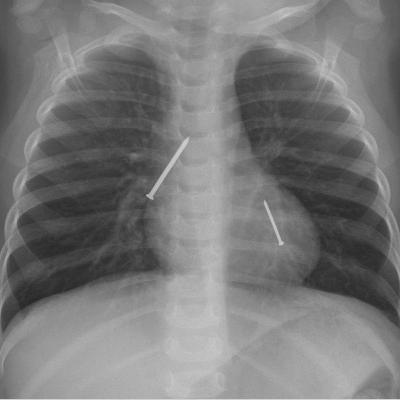

Last time we discussed swallowed foreign objects, today it's INHALED items. Do you know what to do - and NOT do - in an emergency choking situation? What if your child was choking, but now seems fine? Dr. Bee breaks down the types and signs of choking, and what to do for prevent a bad outcome for your child.